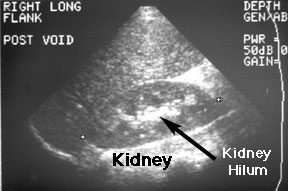

You need to know a few conventions used in ultrasound imaging in order to read ultrasounds. First, try to get as much information about the ultrasound image as you can from the frame. You will see that this image has a label: "RIGHT LONG FLANK POST VOID." This means that you are looking at a longitudinal image of the right flank. The left side of a longitudinal image is always the cephalad side of the image. The right side of a longitudinal image is the caudad side. The kidney is the bean shaped structure marked at either end by a small cursor [+]. Superior to the kidney and superficial (toward the top of the image) is the liver. It is rather homogeneous (fairly regular grey pattern). Notice that the kidney is not so homogeneous. In the center of the kidney is an area of increased echoes (light grey or white). This is the hilum of the kidney also called the central sinus. It shows increased echogenicity because there are several structures (pelvis of the kidney, blood vessels, nerves, fat and lymphatics) that transmit sound differently. As the sound wave hits the interface between two such structures, an echo is generated.